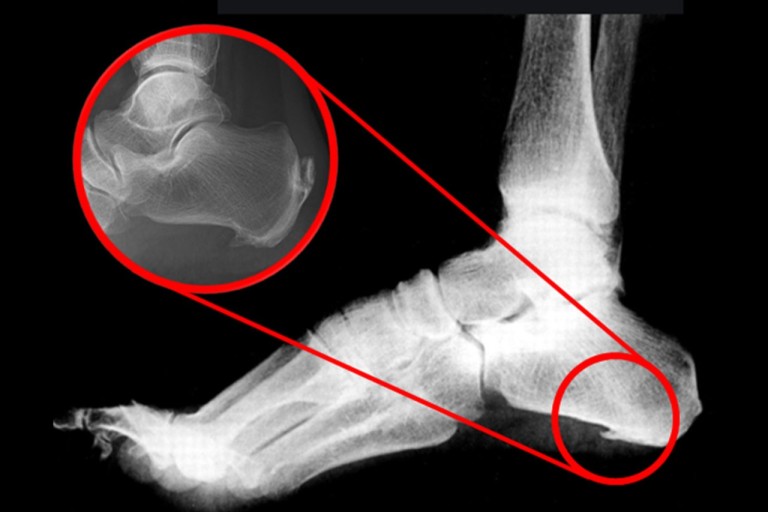

초기에는 밤에만 불편함을 느끼다가 점점 지속 시간도 늘어납니다.3. 족저근막염

발바닥 통증의 대표 질환으로,

발뒤꿈치에서 발바닥 전체로 이어지는 근막에 염증이 생기며

걷거나 서 있을 때 발바닥이 뜨겁고 찌릿한 통증을 유발합니다.

특히 아침에 첫 발을 디딜 때 더 아픈 경우가 많아요.